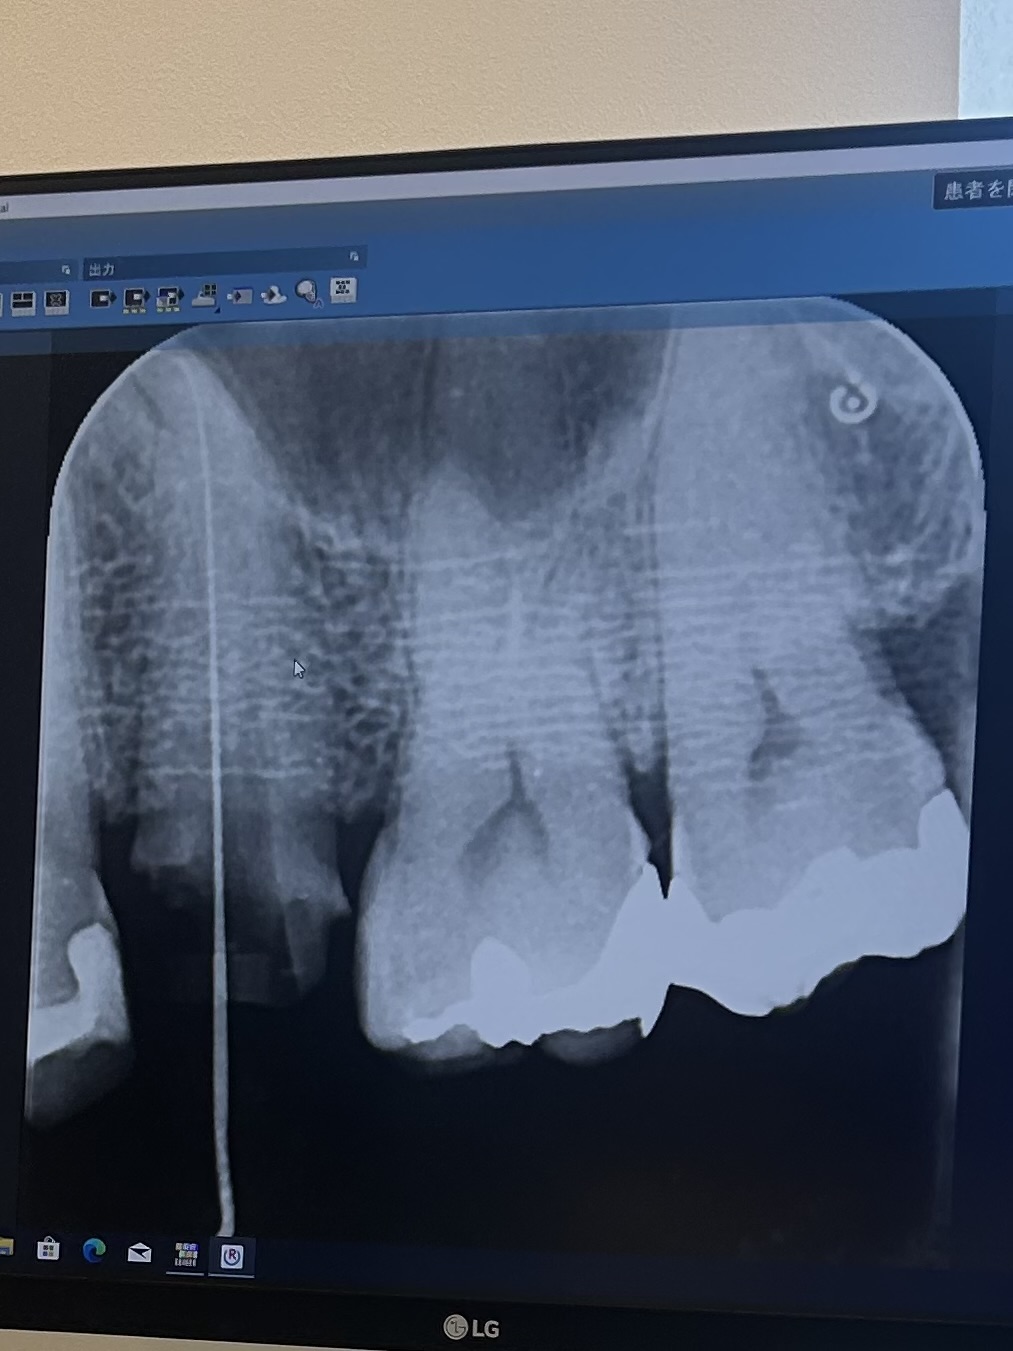

抜髄してから、根の掃除を4回やりましたがまだ叩くと響く症状が取れません。

根の先が曲がっているが、もう少し根気良く掃除をして、もし痛みが取れなければ、大学病院に紹介することもある、とのことでした。

根が曲がっているので、上手く掃除が出来てないのでしょうか。あるいは、欠けたこともある歯なので、割れてるのでしょうか。大学病院に行けば分かるのでしょうか。

レントゲン添付します

画像1

CTの設備があれば2次元画像ではなく3次元で立体的な画像で確認できますから、歯根と根管の状態はよくわかりますから、根管治療の専門医などになれば歯科医院ではCTも揃えていることが多いのではないかと思います。